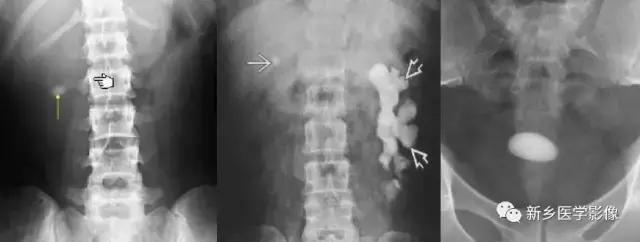

胆结石

可完全钙化,也可以表现为环形钙化,如胆囊切除术也可以导致结石脱落至肝下隐窝。

2

胆囊钙化

多见于慢性胆囊炎、瓷胆囊

尿路结石

常见于尿路阳性结石,可以发生在尿路任何位置,如肾结石、输尿管结石及膀胱结石